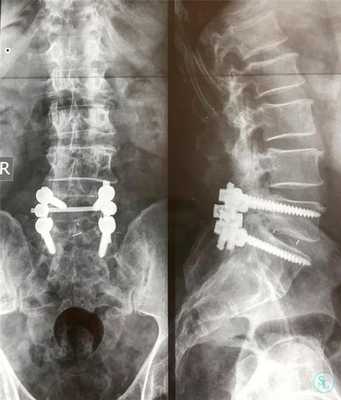

Традиционные открытые хирургические вмешательства при фораминальном стенозе позвоночного канала менее целесообразны, чем минимально инвазивные эндоскопические операции на позвоночнике. Открытые вмешательства при фораминальном стенозе сопряжены с частичным или полным удалением межпозвонкового сустава, более высокими рисками осложнений, значительными послеоперационными рубцами. Более того, традиционная открытая операция требует дополнительной установки металлоконструкций для стабилизации сегмента позвоночника. Восстановление после таких вмешательств более тяжелая и продолжительная. Поэтому нейрохирурги нашей клиники отдают предпочтение эндоскопической фораминотомии при стенозе позвоночного канала и межпозвонковых грыжах. Таким образом удается избежать открытой операции на позвоночнике со всеми ее недостатками, заменив ее нетравматичным минимально инвазивным хирургическим вмешательством.

- Устанавливают опорно-стабилизирующие системы (при необходимости).

Стабилизирующие конструкции

Удаление тел, их отростков и других анатомических структур чревато дестабилизацией подвергшегося вмешательству позвоночно-двигательного сегмента, а также повышению риска развития тяжелых прогрессирующих кифотических и сколиотических деформаций. Причем чаще страдает поясничный и шейный отдел, а также в переходные зоны.

Это обуславливает необходимость часто использовать на завершающем этапе операции методики фиксации позвонков. Особенно они важны при выполнении ламинэктомии у детей и подростков, поскольку в таких случаях ситуация усугубляется асимметричным ростом позвонков.

Одним из способов стабилизации прооперированного позвоночно-двигательного сегмента является спондилодез. Его выполнение подразумевает установку специальных опорно-стабилизирующих конструкций, прочно соединяющих соседние позвонки в области воздействия между собой. В определенных случаях дополнительно требуется провести трансплантацию взятого у пациента из подвздошной кости фрагмента. В результате позвонки плотно срастаются между собой и теряют способность двигаться. Но при проведении ламинэктомии на 1 или 2 позвонках и их спондилодезе пациенты обычно не замечают существенных ограничений при движениях.